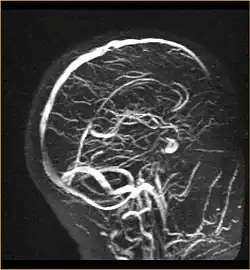

Angiografie der Sinusvenen im MRT

Angiografie bzw. Angiographie (Wortteil Angio- von griechisch ἀγγεῖον ‚Gefäß‘) nennt man in der Medizin die ab 1923/1924 eingeführte radiologische Darstellung von Gefäßen, meist Blutgefäßen mittels diagnostischer Bildgebungsverfahren, beispielsweise Röntgen oder Magnetresonanztomografie (MRT). Hierzu wird häufig ein Kontrastmittel in das Blutgefäß injiziert. Auf dem Bild der aufgenommenen Körperregion zeichnet sich dann der mit dem Kontrastmittel gefüllte Gefäßinnenraum ab. Das resultierende Bild nennt man Angiogramm. Mit der MRT sind auch Angiografien ohne Kontrastmittel möglich, wodurch man sich die invasive Punktion des Gefäßes erspart.

• Magnetresonanzangiografie (MRA)